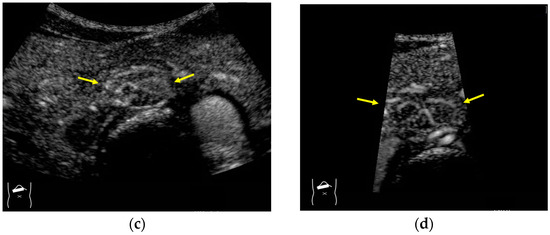

Figure 12.

Manhole-like defect in hemangioma: (a) gray-scale US of the case (arrows: hemangioma); (b) CEUS shows a cotton wool appearance in the periphery of the lesion (arrows): (c) the lesion shows a complete defect in the lesion during observation (arrows); (d) a reasonable explanation of this phenomenon. In hemangioma, destroyed microbubbles are not quickly replaced because of the low blood flow velocity, mimicking a wash-out phenomenon.